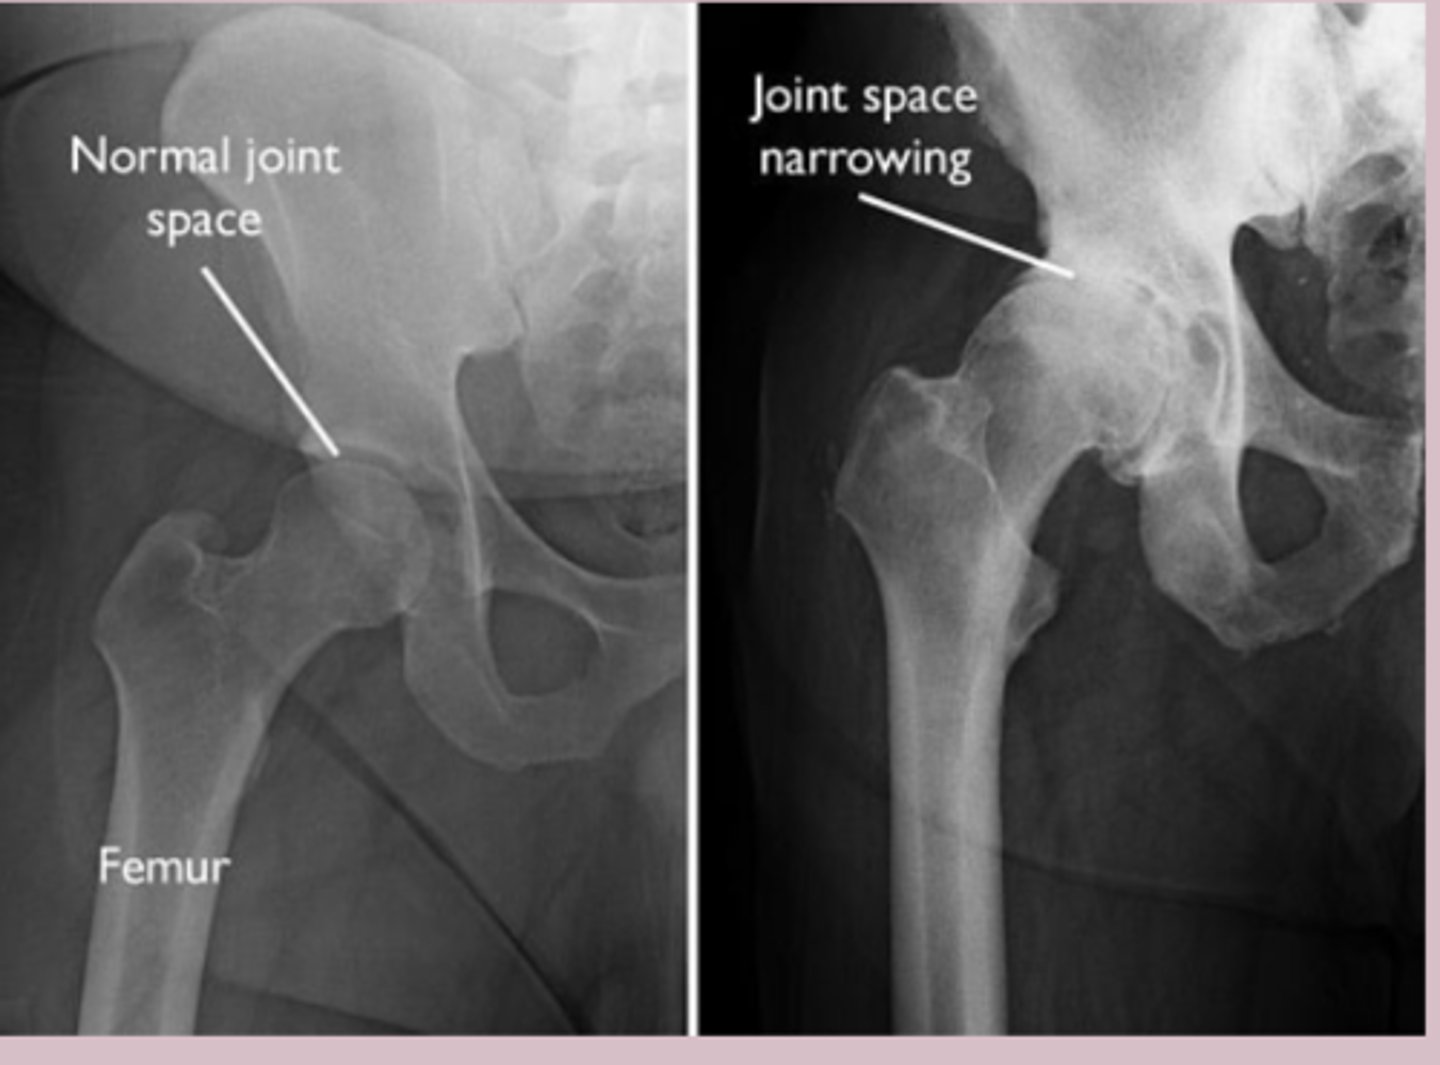

-Xray weight bearing: Asymmetric joint space narrowing

-subchondral sclerosis, osteophytes, subchondral cysts

osteoarthritis dx

-clinical

Imaging